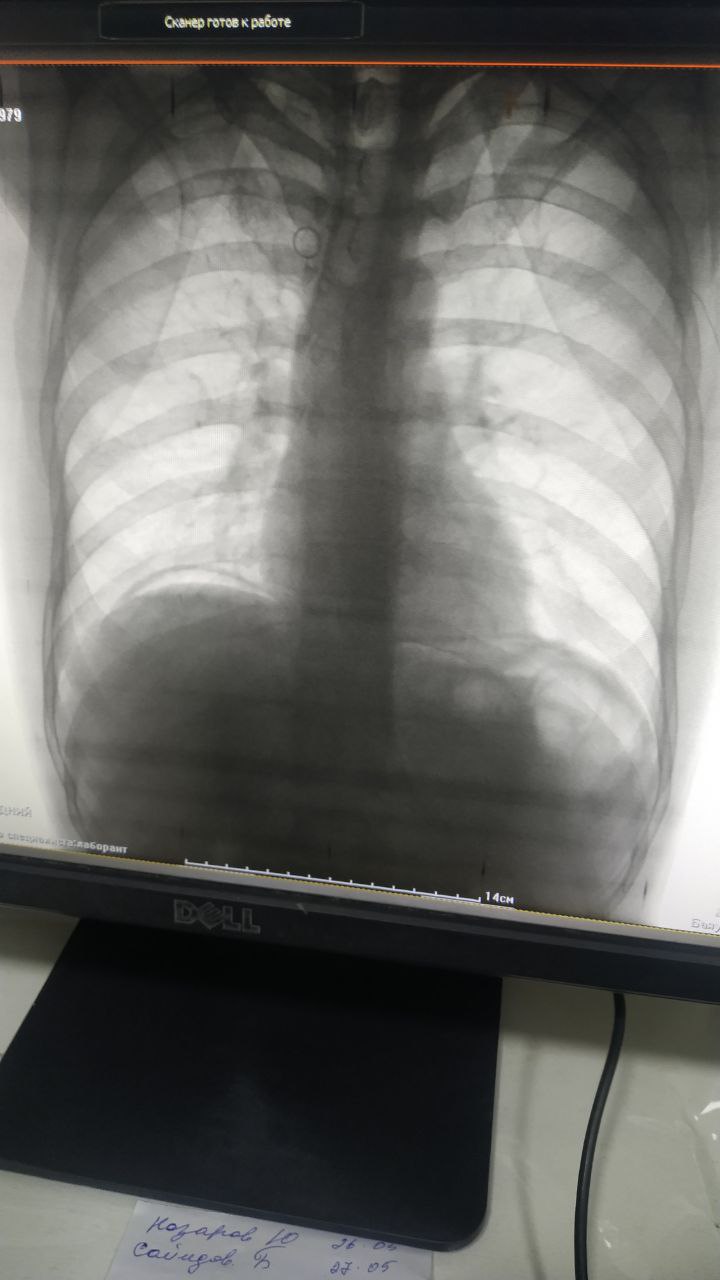

А И in Radiology/Рентгенология Чат

Болной 1979. Боль в области эпигастрия сильно

Возможно перфорация язвы

Свободный газ в брюшной

Анамнеза язва

Серп

Перфорации